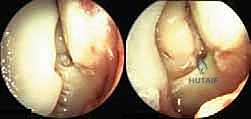

الخطوة الثانية: تنظير المفصل التشخيصي والعلاجي (Arthroscopy)

قبل فتح الجانب الإنسي، يقوم الدكتور هطيف بإدخال كاميرا دقيقة (منظار 4K) من خلال ثقوب صغيرة جداً في مقدمة الكاحل. هذه الخطوة حاسمة لتنظيف المفصل من أي أنسجة ملتهبة، وإزالة أي شظايا عظمية أو غضروفية حرة، ومعالجة أي تقرحات في سطح عظمة الكاحل ناتجة عن عدم الاستقرار.